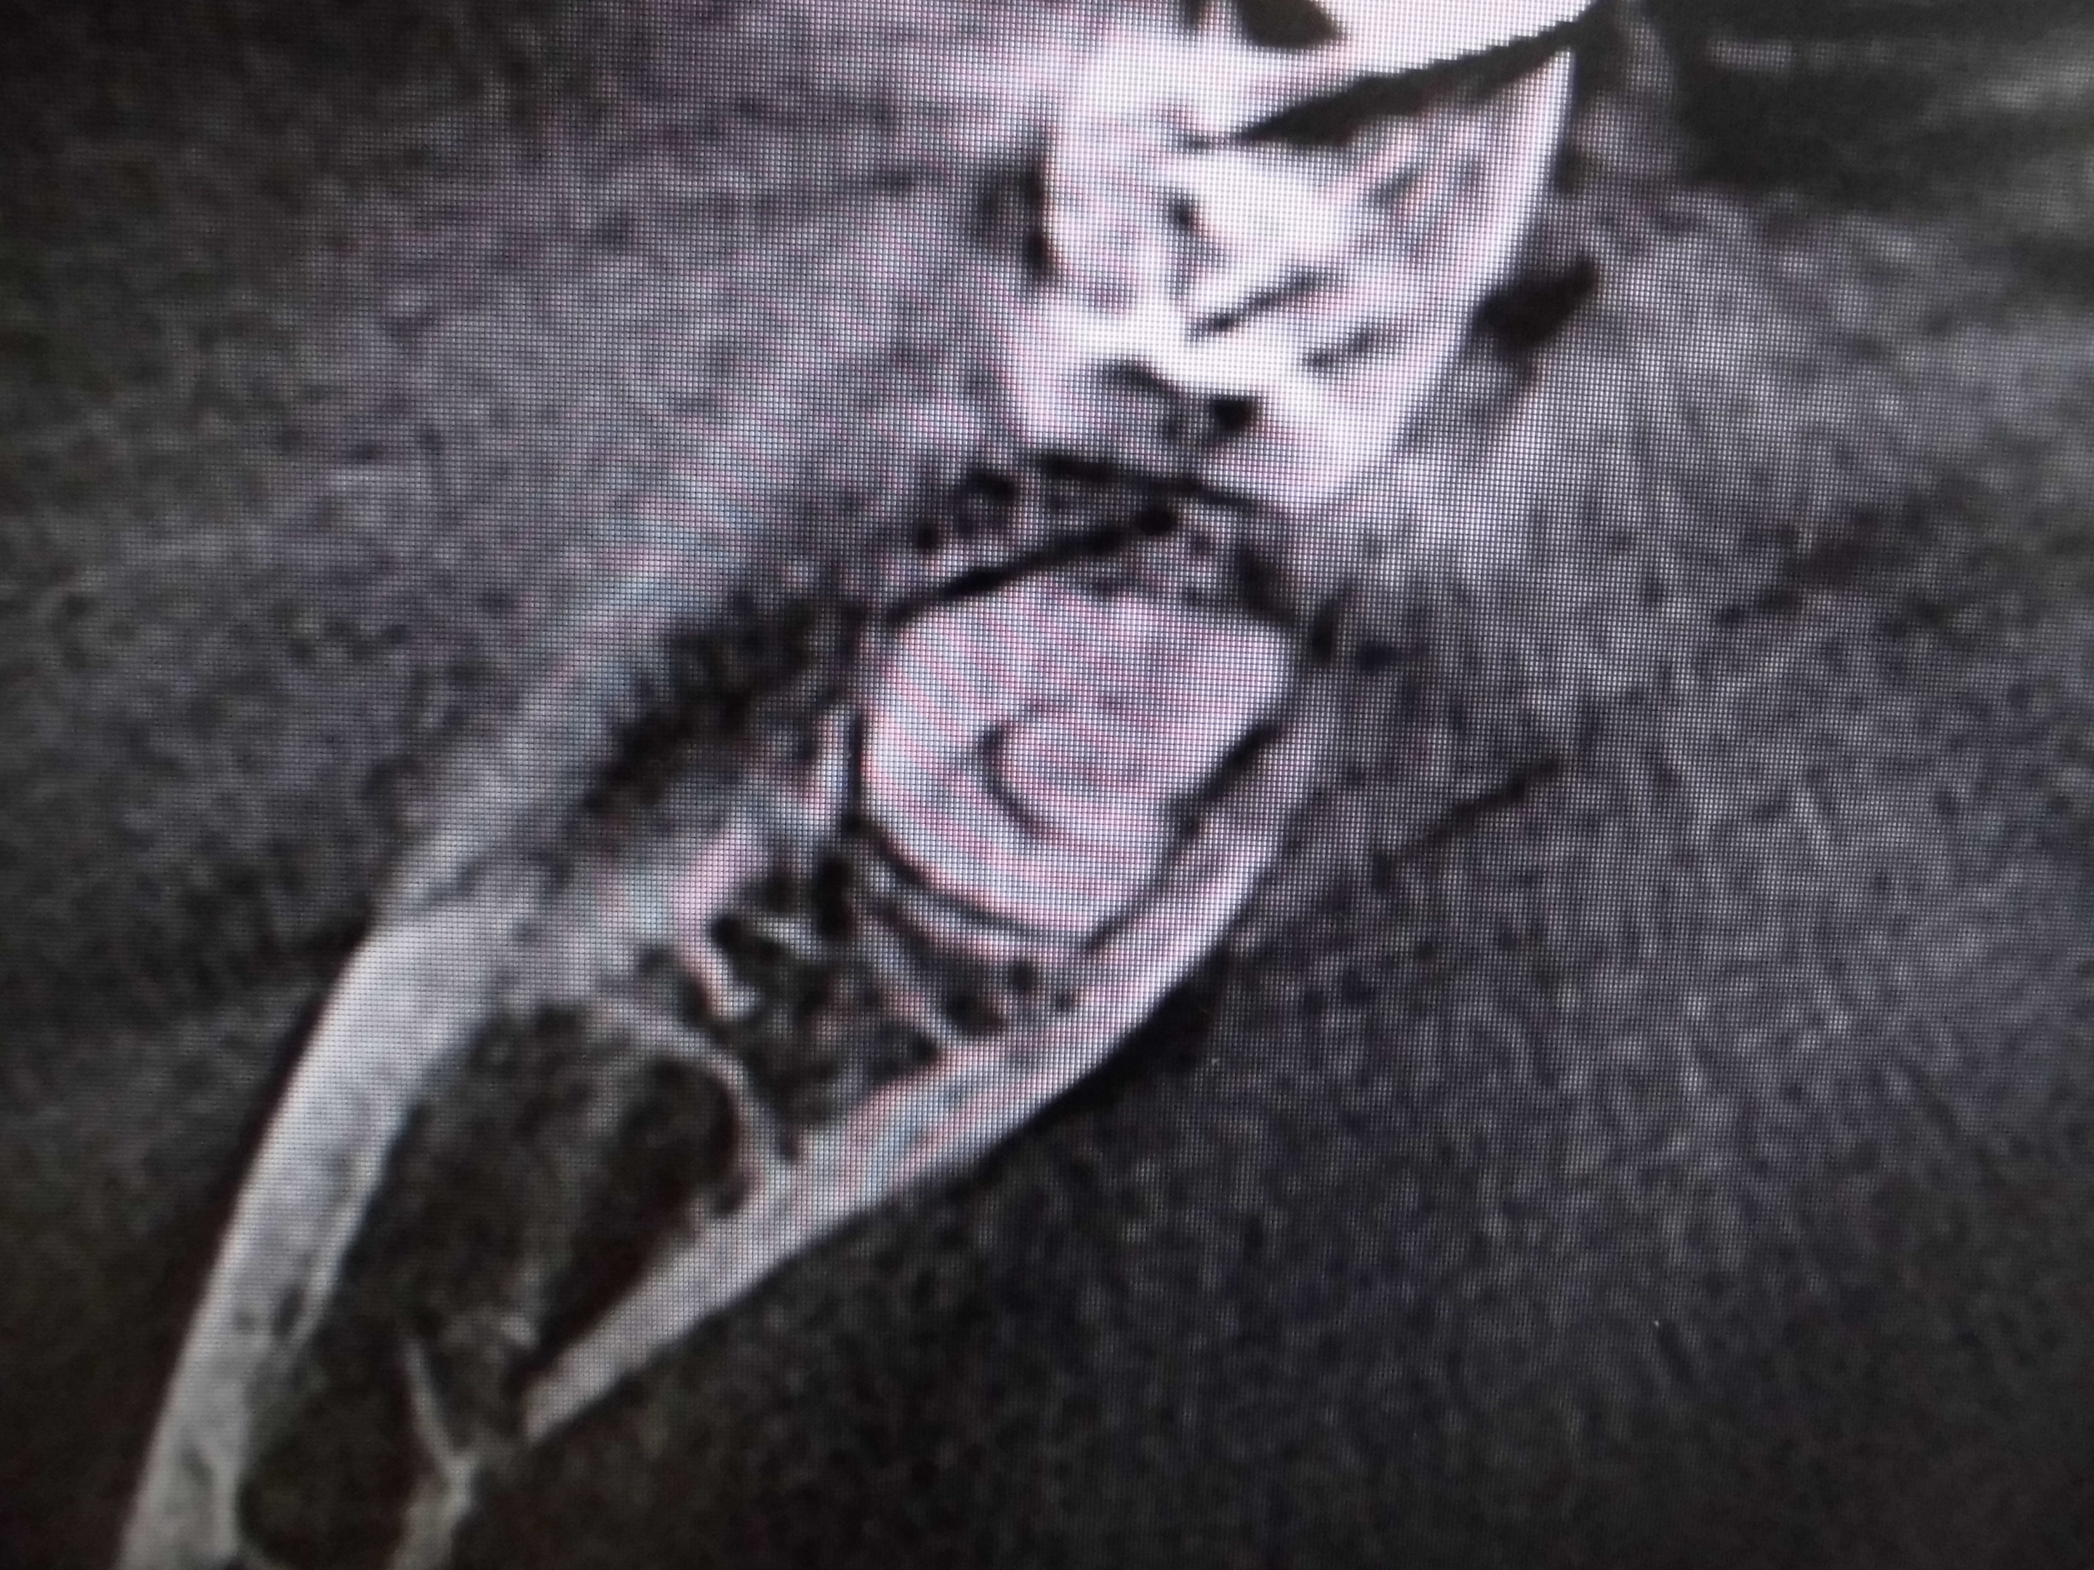

レントゲンでは不明な根尖病巣がCTでははっきり写ります。

同じ患者様です。根管が樋状根になっているのもわかります。